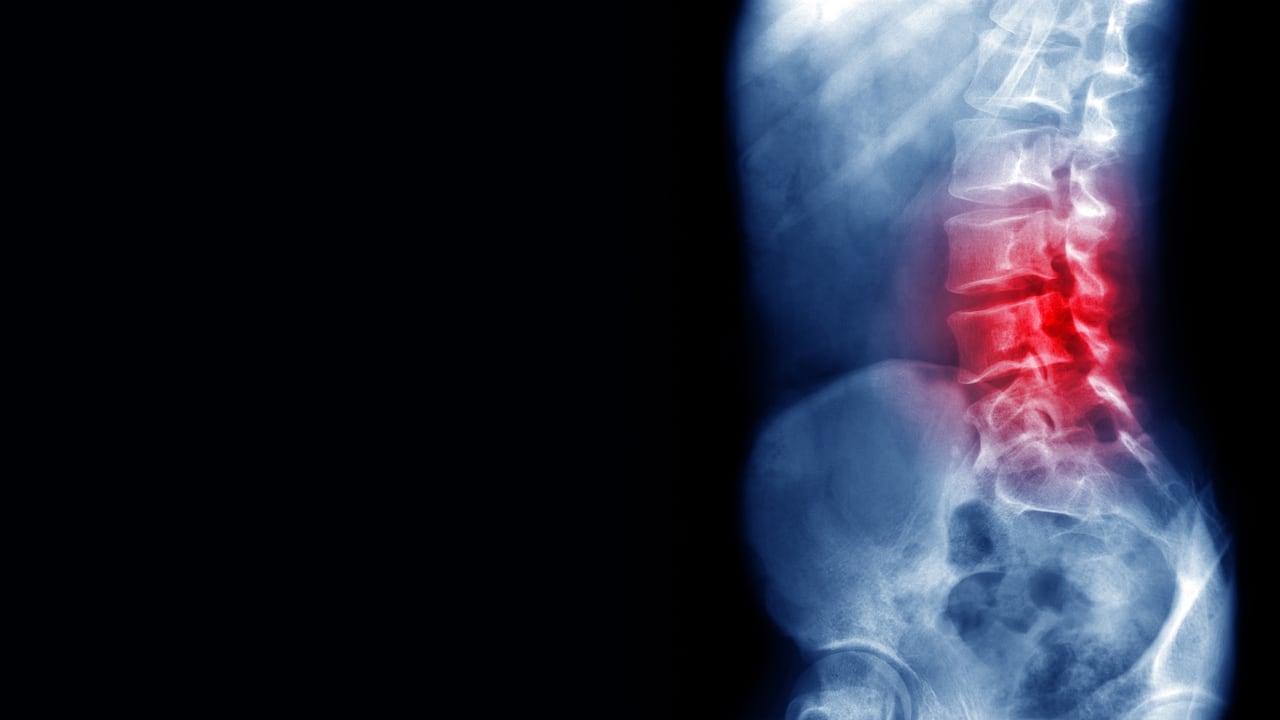

A medida que pasan los años, uno de los dolores más frecuentes que aparece es el dolor de espalda. Si bien después de los 30 años los huesos suelen ser más débiles y susceptibles, este padecimiento traduce a cualquier dolencia que se da a nivel de la columna vertebral.

De hecho, varios estudios científicos han identificado que ocho de cada diez personas en el mundo, suelen tener este tipo de dolor alguna vez en la vida. Además, puede ser causado por hernias que se localicen principalmente en zonas móviles de la columna, como las cervicales y las lumbares, según el Hospital Universitario Clinic Barcelona.

Como tal, esta dolencia en la espalda puede variar desde una molestia sorda, constante, hasta un síntoma súbito e intenso. Cuando se presenta un dolor agudo, este puede aparecer repentinamente y suele durar algunos días o semanas; en cambio, cuando se trata de un dolor de espalda crónico, este puede durar más de tres meses, según el portal oficial especializado en salud Medline Plus.

Entre las afecciones que hace referencia a esta dolencia está la lumbalgia, que es el dolor localizado en la parte inferior o baja de la espalda, cuyo origen tiene que ver con la estructura músculo-esquelética de la columna vertebral. “La lumbalgia se define como dolor muscular en la zona lumbar, que conlleva un aumento del tono y de la rigidez muscular”, explica al portal Cuídate Plus.